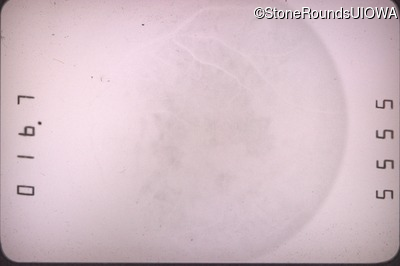

Fluorescein Angiography - Right - 20/100 -1

Exemplar